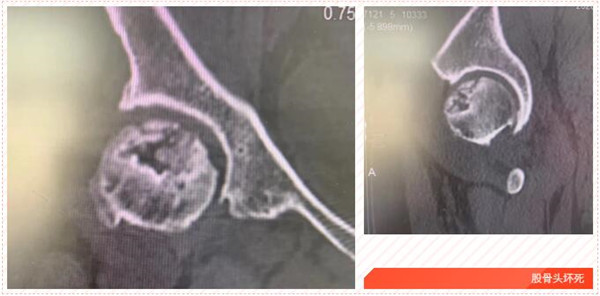

五年前,家住岱山的洪女士發(fā)覺自己的髖部經(jīng)常疼痛,有時(shí)候活動都受影響,特別時(shí)久行后更是疼痛難忍,便到我市某院就診,經(jīng)檢查診斷為“雙側(cè)股骨頭壞死”,予以口服藥物等保守治療,可并沒有好轉(zhuǎn)。

2017年5月,在朋友的建議下,洪女士來到我院,經(jīng)CT診斷雙側(cè)股骨頭無菌性壞死。便在危立軍副院長的建議下,做了左髖關(guān)節(jié)置換術(shù)。術(shù)后,洪女士恢復(fù)良好。